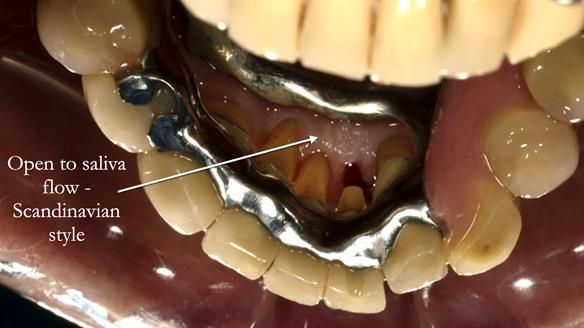

Instead, we made a Scandinavian-style, metal-based lower RPD.

It was made promptly, then relined gradually over the following year

to optimise fit, comfort, and support.

It’s worth saying that the lower denture in this case was made in the early days of Rowan and me using the Scandinavian approach. Rowan cast the metalwork himself for this denture.

Looking back, we would make this denture more hygienic now. The design and finish would be more refined and delicate, particularly when compared with the upper metalwork, which was made later using Chris Hesketh’s chrome work. I will discuss this in detail at the study club.

That said, the lower denture worked beautifully. It did exactly what it was meant to do, even though, by today’s standards, it looks a little agricultural.